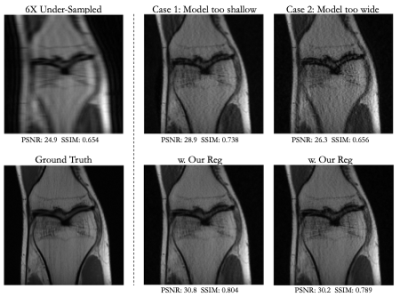

Visual and numerical results for the multi-coil knee and brain datasets under 4x and 6x acceleration are shown in Figs. 2-5 and Tab. 1. We tested U-Net architectures with typical widths (128 vs. 256 channels) and depths (3 levels vs. 5 levels). Additional results for total-variation (TV) regularized DIP [7] are shown in Tab 1. Figs. 2-5 indicate that suboptimal architectures lead to severe artifacts in the reconstructed images (top rows). Utilizing our regularization strategy, we observe appreciable improvements in image quality over the baselines, especially for 4x acceleration. Notably, the extent of improvement is similar regardless of the architecture. This suggests that controlling the frequency biases of the network architecture via proper regularization might be as effective as modifying the architecture in DIP based reconstruction. In contrast, TV regularization does not exhibit comparable performance. Our strategy works consistently on MR images acquired from different organs (i.e., knee and brain).

Fig 2. Results for a 4x under-sampled multi-coil knee scan. Our regularization strategy improves reconstruction over architectures that are too shallow (3-level UNet) or too wide (256 channels/layer).

Fig 3. Results for a 6x under-sampled multi-coil knee scan. Our regularization strategy improves reconstruction over architectures that are too shallow (3-level UNet) or too wide (256 channels/layer).